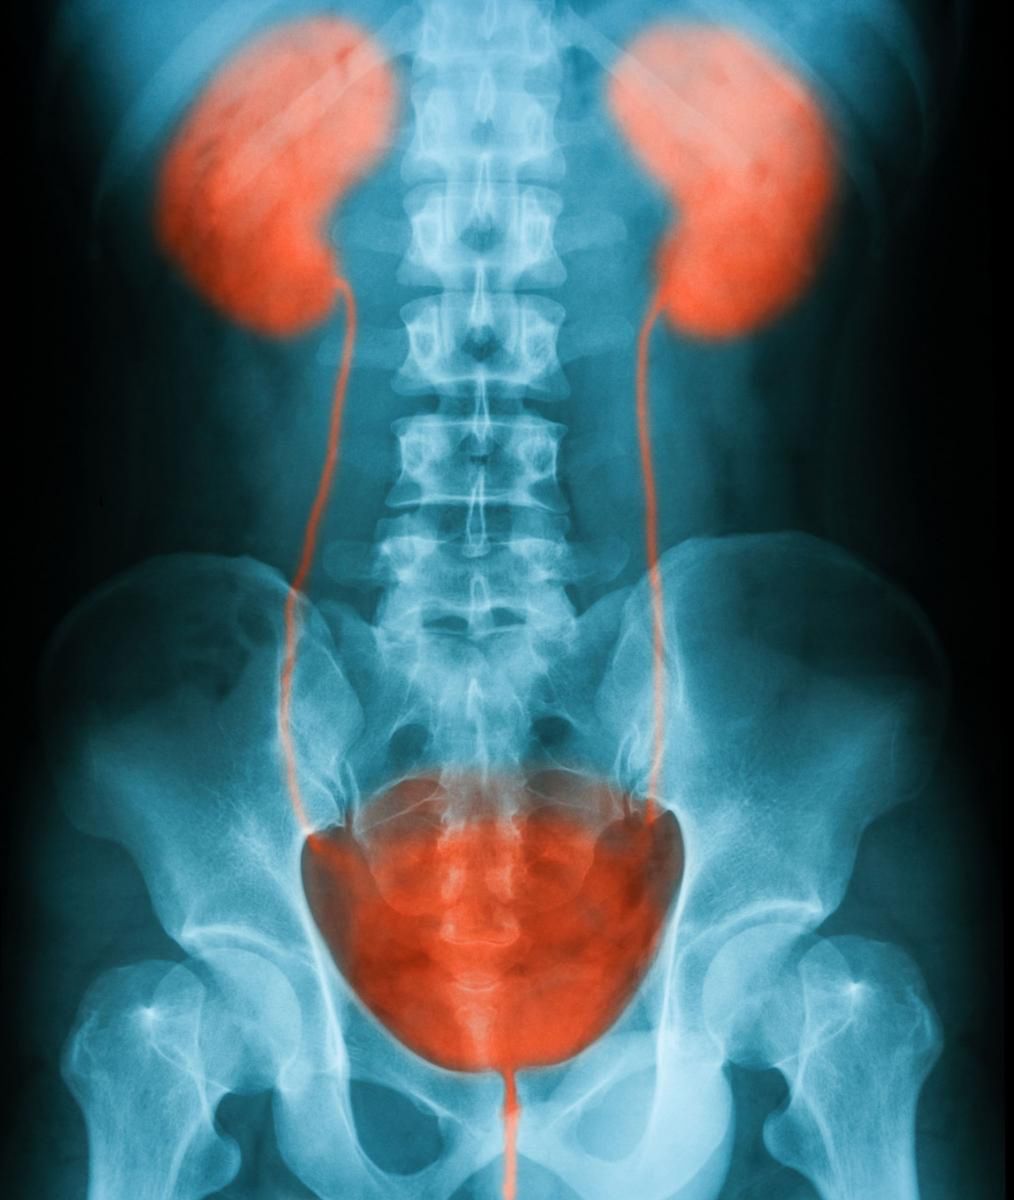

Urografia polega na dokładnym obrazie układu moczowego. Jeżeli badanie USG nie jest zbyt precyzyjnie, wówczas lekarz może zalecić wykonanie badania RTG z kontrastem - urografii. Układ moczowy odpowiada za wydalanie moczu z organizmu. Na jego pracę wpływają nerki, pęcherz, cewka moczowa oraz moczowody.

Urografia to badanie umożliwiające dokładną obserwację narządów układu moczowego – ich budowy i pracy, a także ewentualnych zmian i nieprawidłowości.

Urografia to badanie rentgenowskie z kontrastem. Kontrast to środek cieniujący, który zażywa się przed badaniem. Kontrast przedostaje się wraz z krwią do nerek, następnie do moczu i dalej do kolejnej części układu moczowego.

Pierwsze zdjęcie RTG, nazywamy fazą nefrograficzną, przedstawia ilość nerek, ich położenie i kształt. Lekarz może również zobaczyć, czy w nerkach nie ma kamieni. Urografia pozwala również zoabczyć, czy nerki pracują prawidłowo. Jeżeli nie pracują w tym samym czasie lub jeżeli coś blokuje ich pracę, będzie to widoczne na zdjęciach. Dzięki zażyciu kontrastu, widoczny jest przepływ moczu przez moczowody do pęcherza.

Na zwykłym badaniu USG nie zobaczymy moczowodów, które mogą być poszerzone i nieprawidłowo się układają. Może to być przyczyną gromadzenia się w moczowodzie moczu, a co za tym idzie – powstawania stanów zapalnych. Dzięki zastosowaniu urografii można dostrzec w moczowodzie kamień, który blokuje przepływ moczu do pęcherza.

Ostatnią fazą badania urografii jest zbadanie moczu, który wypełnia pęcherz. Zdjęcie RTG z kontrastem pokazuje ściany pęcherza i ich ewentualne zmiany. Badanie umożliwi również dostrzeżenie cieni powiększonej prostaty. Co więcej, urografia pokazuje, czy po wypróżnieniu mocz nie pozostał w pęcherzu.

Wynikiem badania jest zestaw zdjęć oraz opis lekarza radiologa. Urografia trwa około 30 minut. Pierwsze zdjęcie jest bez kontrastu i dotyczy jamy brzusznej. Kolejne wykonuje się już po podaniu dożylnie środka cieniującego – nerki, układ kielichowo-miedniczkowy, moczowody i pęcherz. Powyższe zdjęcia wykonuje się w pozycji leżącej. Kiedy mocz znajduje się już w pęcherzu, robi się zdjęcie na stojąco, aby zobaczyć jak obniża się pęcherz, gdy jest pełny. Ostatnie zdjęcie RTG wykonuje się po opróżnieniu. Dzięki temu lekarz może zobaczyć, czy pęcherz jest całkowicie pusty, czy też mocz zalega. Zalegający mocz w pęcherzu jest widoczny u mężczyzn z przerostem gruczołu krokowego.